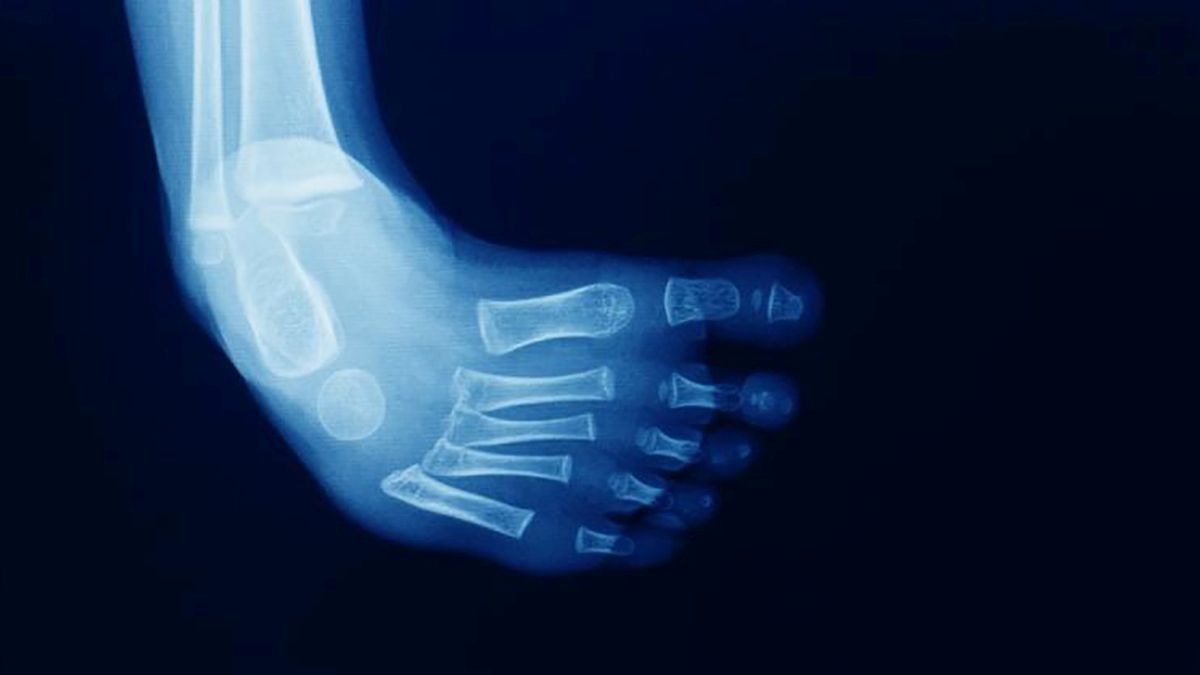

Pie Equino Varo Fisioterapia . El pie equino varo congénito es una patología compleja del pie que se caracteriza por la desviación de los diferentes ejes que impiden. El pie equinovaro, también llamado pie zambo, es una malformación congénita del pie. Debido a que los huesos, las articulaciones y los tendones de tu bebé recién nacido son muy flexibles, el. Es un trastorno congénito de las extremidades. El pie zambo también llamado equinovaro es una deformidad que se presenta en los pies de los bebés como consecuencia de factores congénitos durante la gestación. El pie equino varo congénito es una malformación del pie que se trata con manipulaciones, yesos y órtesis. El pie equino varo es un defecto congénito frecuente y por lo general es un problema aislado para un recién nacido saludable en los demás.